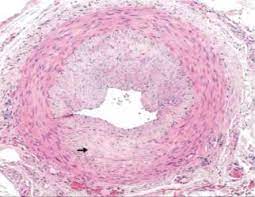

La polimialgia reumática y la arteritis de células gigantes comparten similitudes genéticas y perfiles de citoquinas, lo que sugiere una posible conexión etiológica entre ambas enfermedades. Además, la ACG, una panarteritis sistémica, afecta predominantemente a los vasos de tamaño mediano y grande, incluyendo la arteria temporal y sus ramificaciones extracraneales, así como la aorta y sus principales ramificaciones. Históricamente, la ACG se denominaba arteritis temporal debido a la afectación común de la arteria temporal, aunque también afecta a otras arterias.

La coexistencia frecuente de PMR y ACG en pacientes refuerza la hipótesis de que estas enfermedades podrían representar un espectro de una misma enfermedad, con manifestaciones clínicas variadas. La afectación de la arteria temporal y otras arterias extracraneales es una característica distintiva de la ACG, pero la participación de la aorta y sus ramificaciones también es común en esta enfermedad.

Por otro lado, la arteritis de células gigantes es una vasculitis sistémica que afecta a vasos de tamaño mediano y grande, lo que puede llevar a complicaciones graves como la ceguera debido a la afectación de las arterias oftálmicas. Además, la ACG puede comprometer la aorta y sus principales ramificaciones, incluidas las arterias carótidas extracraneales, lo que puede resultar en aortitis y otras complicaciones vasculares de gran envergadura. Esta capacidad de la ACG para afectar arterias de mayor calibre y sus ramificaciones distingue claramente esta condición de la PMR.